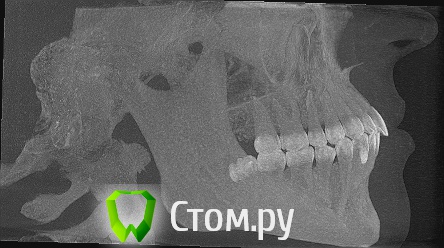

Дарья87 Опубликовано 13 мая, 2014 Автор Поделиться Опубликовано 13 мая, 2014 Еще есть снимки может кто то что то сможет прояснить.Возможно здесь есть хороший специалист.Нуждаюсь в совете.За раннее спасибо! Ссылка на комментарий

Дарья87 Опубликовано 13 мая, 2014 Автор Поделиться Опубликовано 13 мая, 2014 Восьмой зуб который на снимке его уже нет.Удалила так как он не мог выйти на поверхность и встать в зубной ряд Ссылка на комментарий